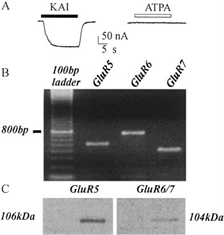

Espressione dei Recettori Neurotrasmettitoriali Umani

Lo studio introduce un modello innovativo per lo studio dell’epilessia,...